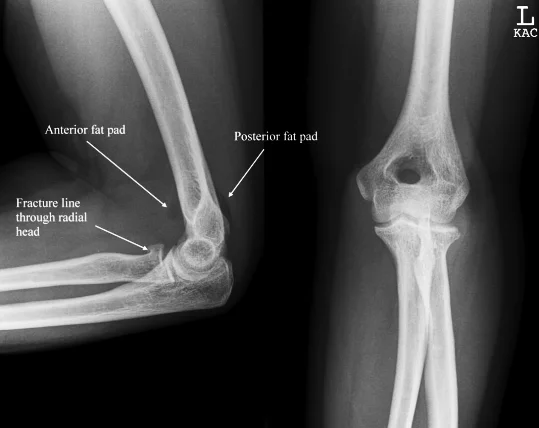

X-ray

- A visible posterior fat pad on the lateral view of the elbow is a sign of occult intra-articular trauma